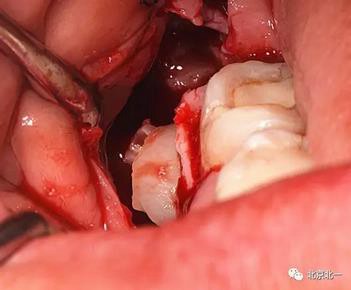

圖六:切開翻瓣, 看見骨面清晰,未見智齒

圖七:去骨后看不見牙齒位置方向。顏色無法區(qū)分,拍片確認(rèn)一下剛才去骨的以及截的冠就是智齒。

圖八:把牙根優(yōu)先取出后還是看不見牙冠在哪里,實(shí)在貼的神經(jīng)管太近, 只能再次拍一個(gè)cbct確認(rèn)。

圖十:實(shí)際情況:看到么在第二磨牙頰側(cè)接近近中區(qū)域。關(guān)鍵牙顏色和骨顏色一致, 只有牙冠部分是白色能看出來, 但是它卻深深的把頭埋下。